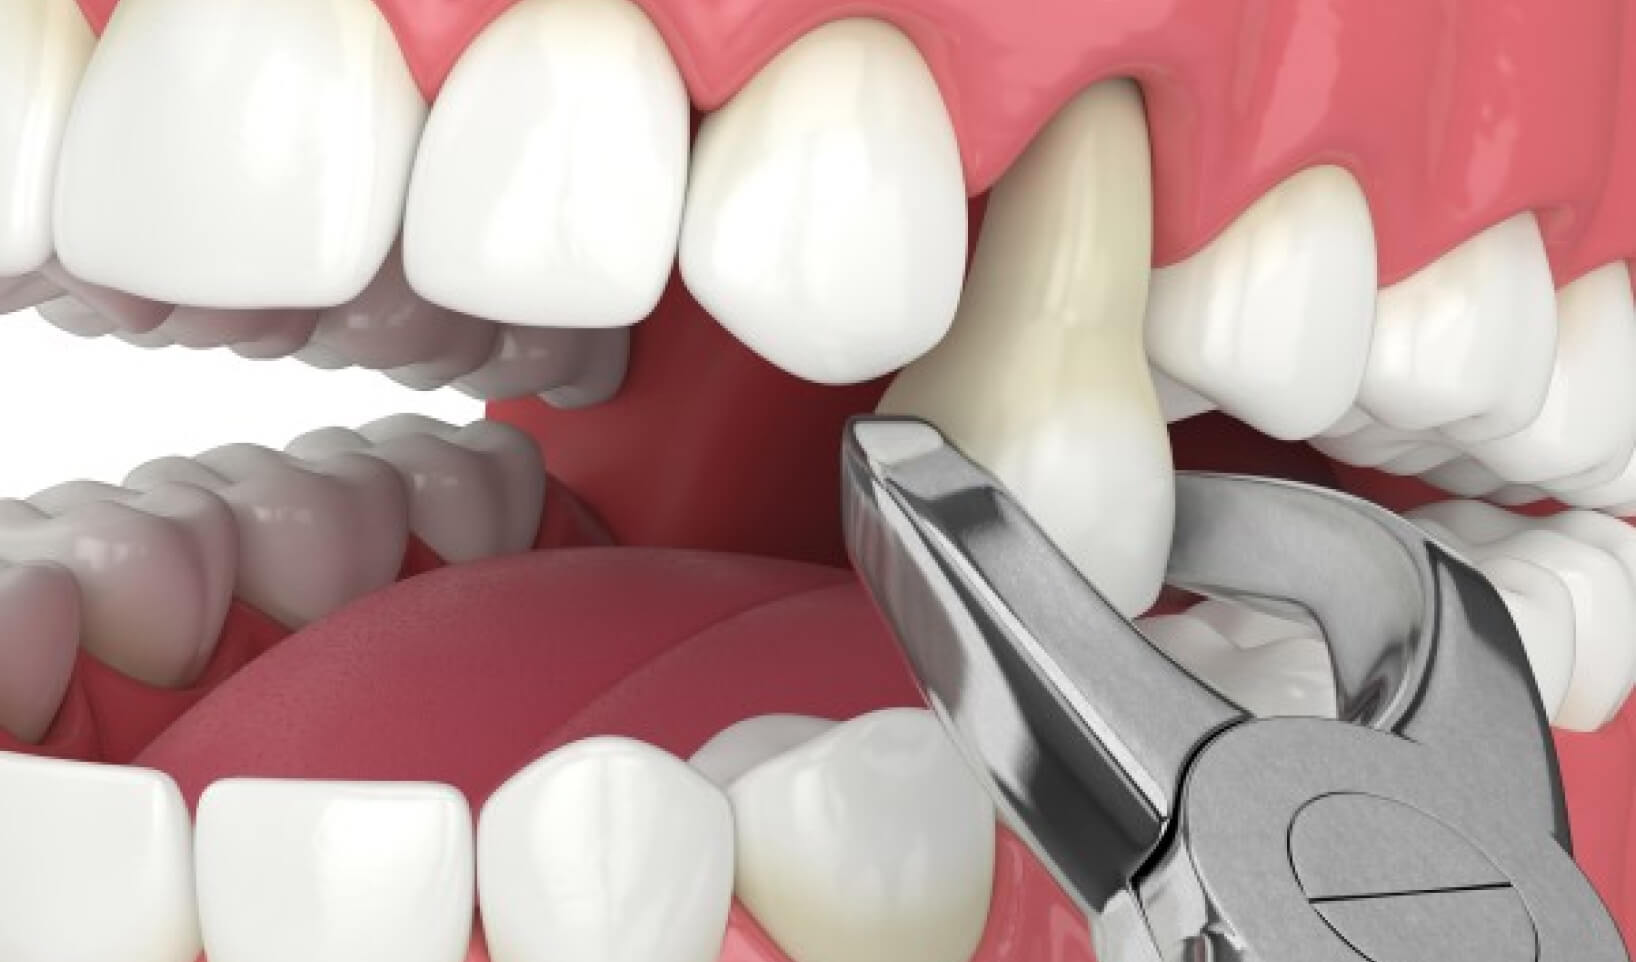

How does it work?

Before pulling the tooth, we will give you an injection of a local anaesthetic to numb the area where the tooth will be removed. If the tooth is impacted, we will cut away gum and bone tissue that covers the tooth and then, using forceps, grasp the tooth and gently rock it back and forth to loosen it from the jaw bone and ligaments that hold it in place. Sometimes, a hard-to-pull tooth must be removed in pieces.

Does it hurt?

There is little point in dressing up the fact that tooth extraction is one of the more demanding dental procedures in terms of the patient experience, though before pulling the tooth we will give you an injection of a local anaesthetic to numb the area where the tooth will be removed.

Our aim is always to ensure the comfort of the patient as best as our skills and the latest technology allow. In some instances, we may suggest intravenous sedation.